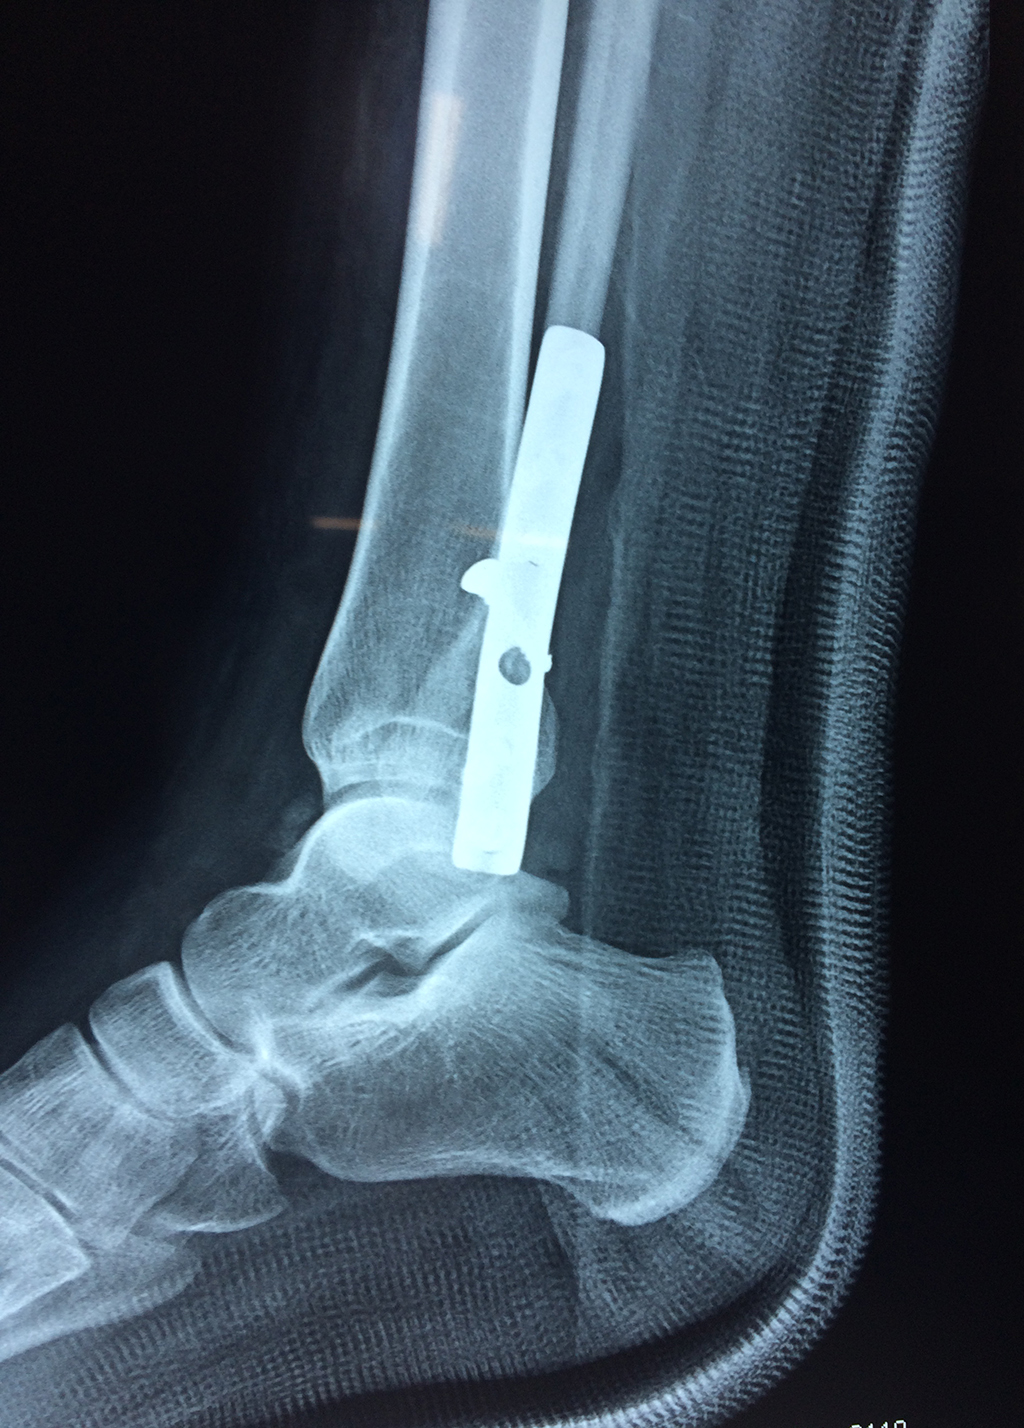

Cuando se necesita cirugía, es probable que esta implique el uso de clavijas de metal, tornillos o placas para sostener los huesos en su lugar mientras la fractura se consolida. Los elementos de soporte pueden ser temporales o permanentes.

De esta forma nos ponemos a tus órdenes, somos conocedores de estos tipos de problemas, visitarnos será un gusto el poderte ayudar. cualquier inquietud puedes escribirnos al correo Esta dirección de correo electrónico está siendo protegida contra los robots de spam. Necesita tener JavaScript habilitado para poder verlo.